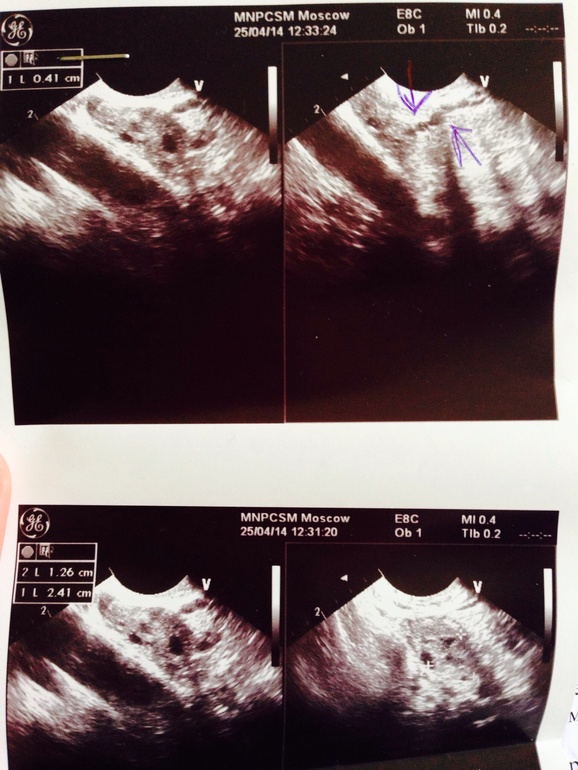

Гидросальпинкс-ну что опять за напасть!?Начиталась в инете что грозит бесплодием ВБ,после лечения трубы долго не восстанавливаются,ворсинки яйцеклетку не продвигают ,ну что за фигня постоянно !!!!Я вовремя взялась за лечение ,у меня все только подозрение на начало воспаления ,в этом цикле не получилось забеременеть ,но у меня 3 Дз ,вчера была у Г.и на узи ...почему постоянно какие -то проблемы ???я не пью ,не курю ,веду здоровый образ жизни ,откуда постоянно эти болячки и угрозы отовсюду о бесплодии !!!! Достало это все ! Девочки ,у кого был этот Гидросальпинкс и вы потом спокойно забеременели и родили ?пожалуйста,успокойте ,не могу уже !!(если кто разбирается в узи обтяните нормальным языком ,а то гениколога я не очень поняла ,она сказала ничего страшного у меня нет ,а я такого вычитала !!!(((((